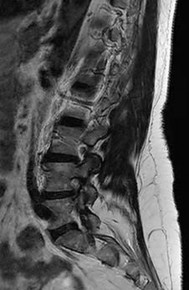

Question 13:

A 65-year-old male presents with neurogenic claudication. He reports pain radiating down both legs when walking, which is relieved by leaning forward on a shopping cart. MRI shows severe spinal stenosis at L4-L5. Which ligament thickens and contributes significantly to the dorsal compression of the thecal sac in this condition?

Correct Answer: Ligamentum flavum

Explanation:

In degenerative lumbar spinal stenosis, hypertrophy and buckling of the ligamentum flavum commonly cause dorsal compression of the thecal sac.